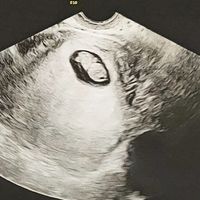

Hola! Me he animado a abrir el post y espero que poco a poco seamos muchas 🤰🏼. Yo vi mi positivo el pasado sábado y mi FPP es el 11 de Mayo. Todavía estoy de muy poquito y al ser primeriza total me...